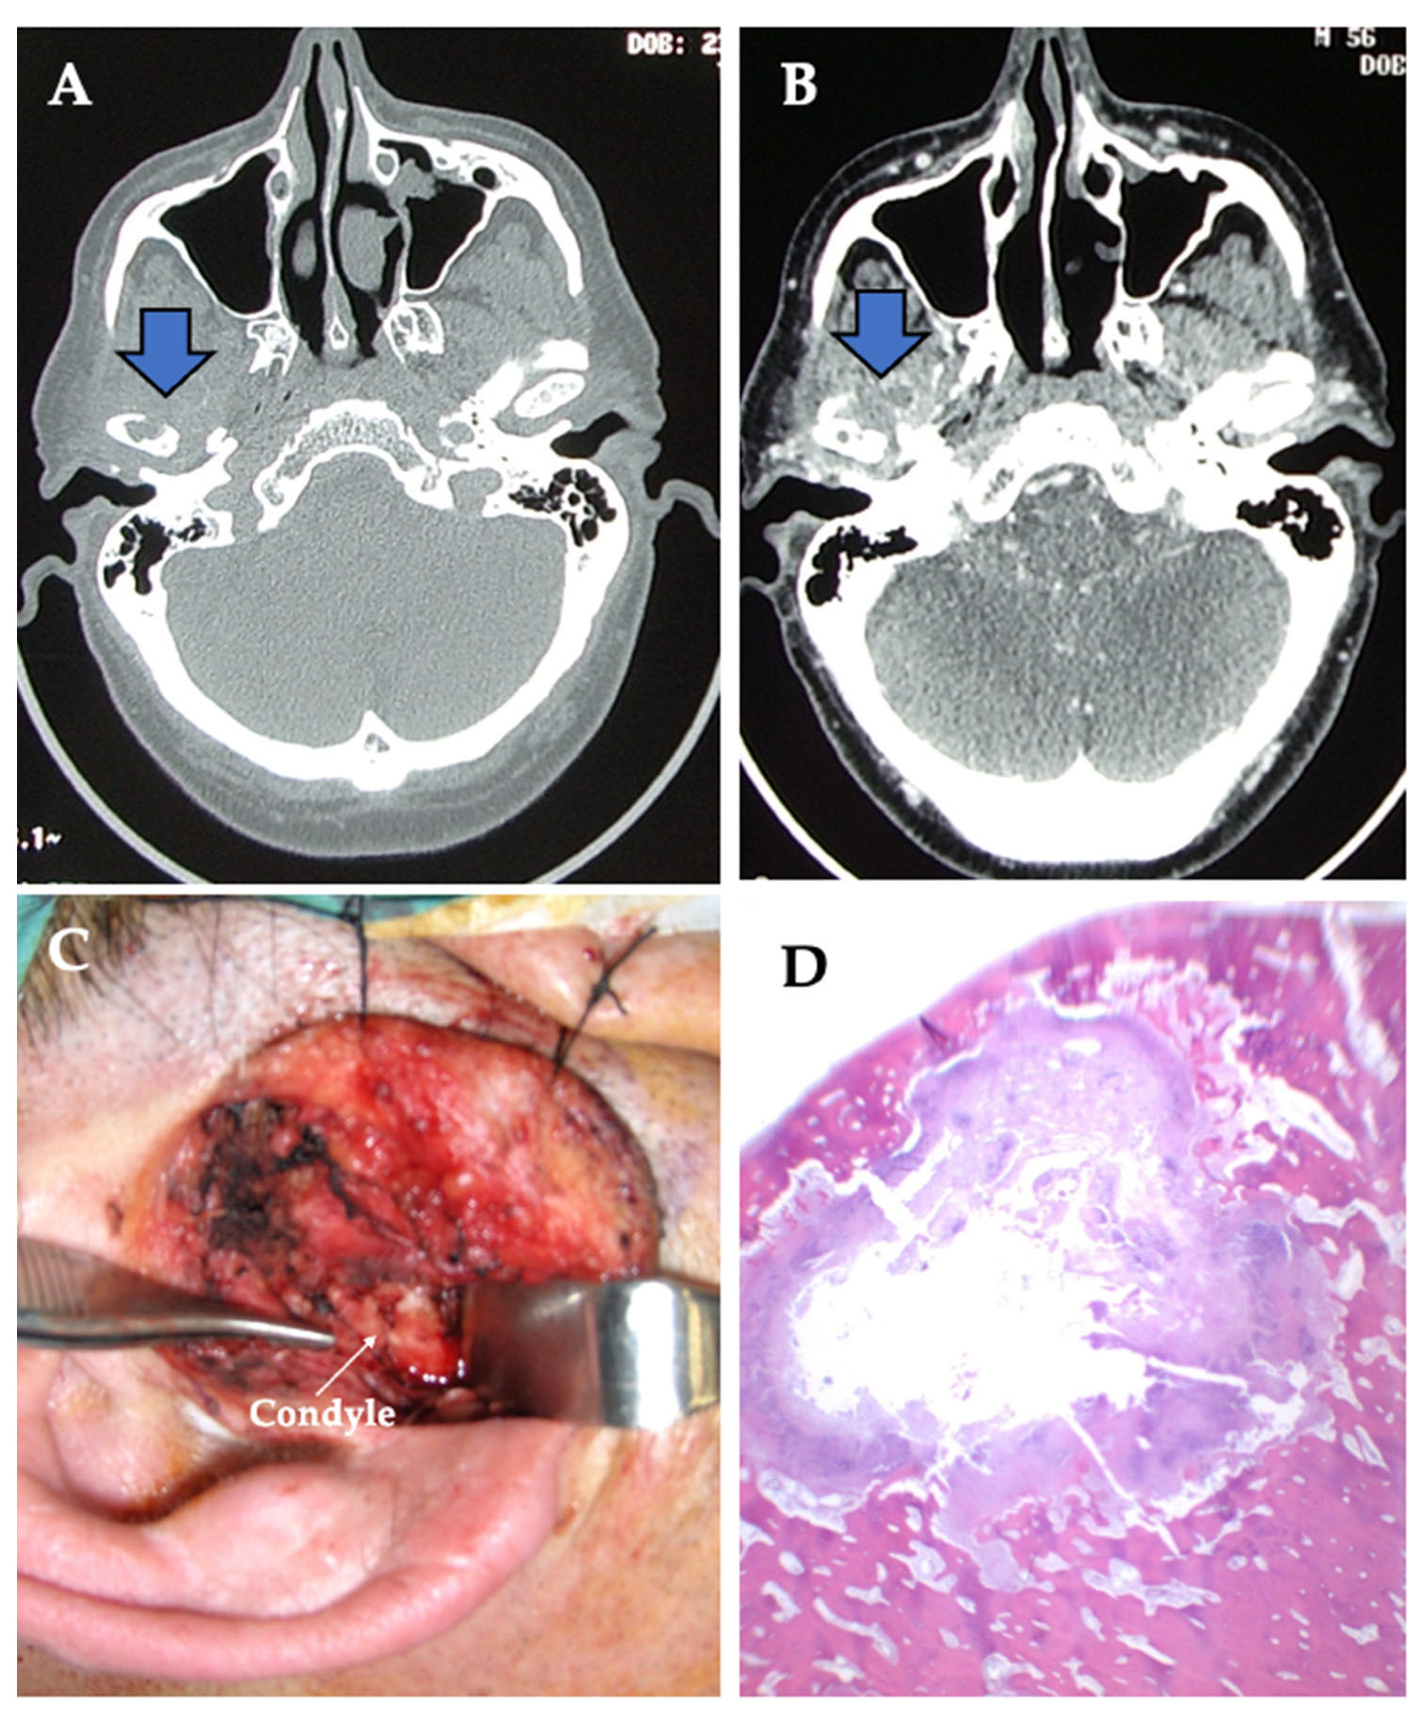

| 3 | 57/M | Posterior open bite | Bone destruction | 8 | 0 | 4.2 | 4.8 | Chondrosarcoma | Right |